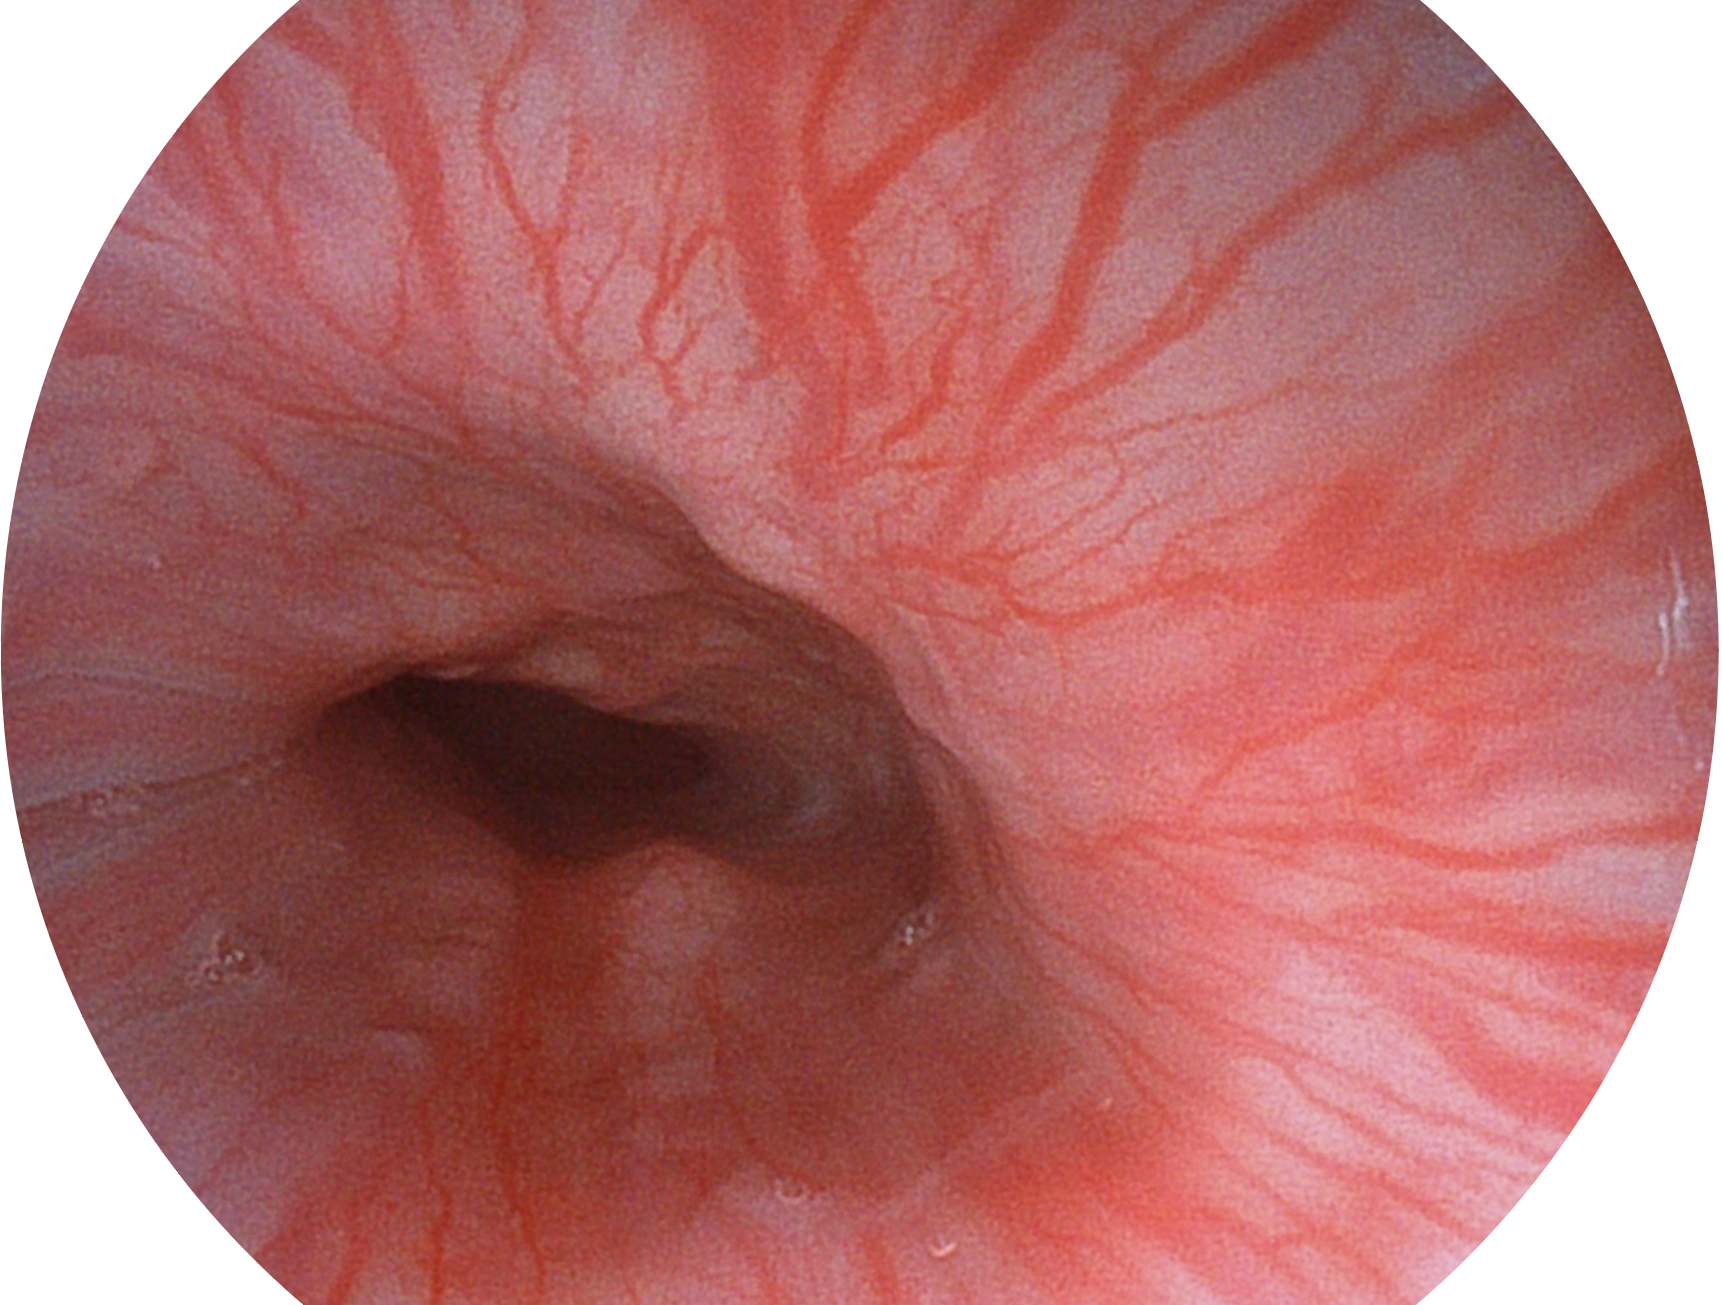

九州酷游新开发的内镜染色技术,主要是基于多波长LED 光源的开发,VLS-55Q 四波长LED 光源是由四个不同颜色的LED光按照相应照明模式所规定的特定发光比例进行合束后形成,合束后形成的照明光的光谱由红光、绿光、蓝光及蓝紫光这四个不同的波段范围构成。具有更高光谱自由度,通过光谱比例的控制,实现了聚谱成像技术,英文全称为“Spectral Focused Imaging, SFI”,缩写为“SFI”和光电复合染色成像技术,英文全称为“Versatile Intelligent Staining Technology, VIST”,缩写为“VIST”。